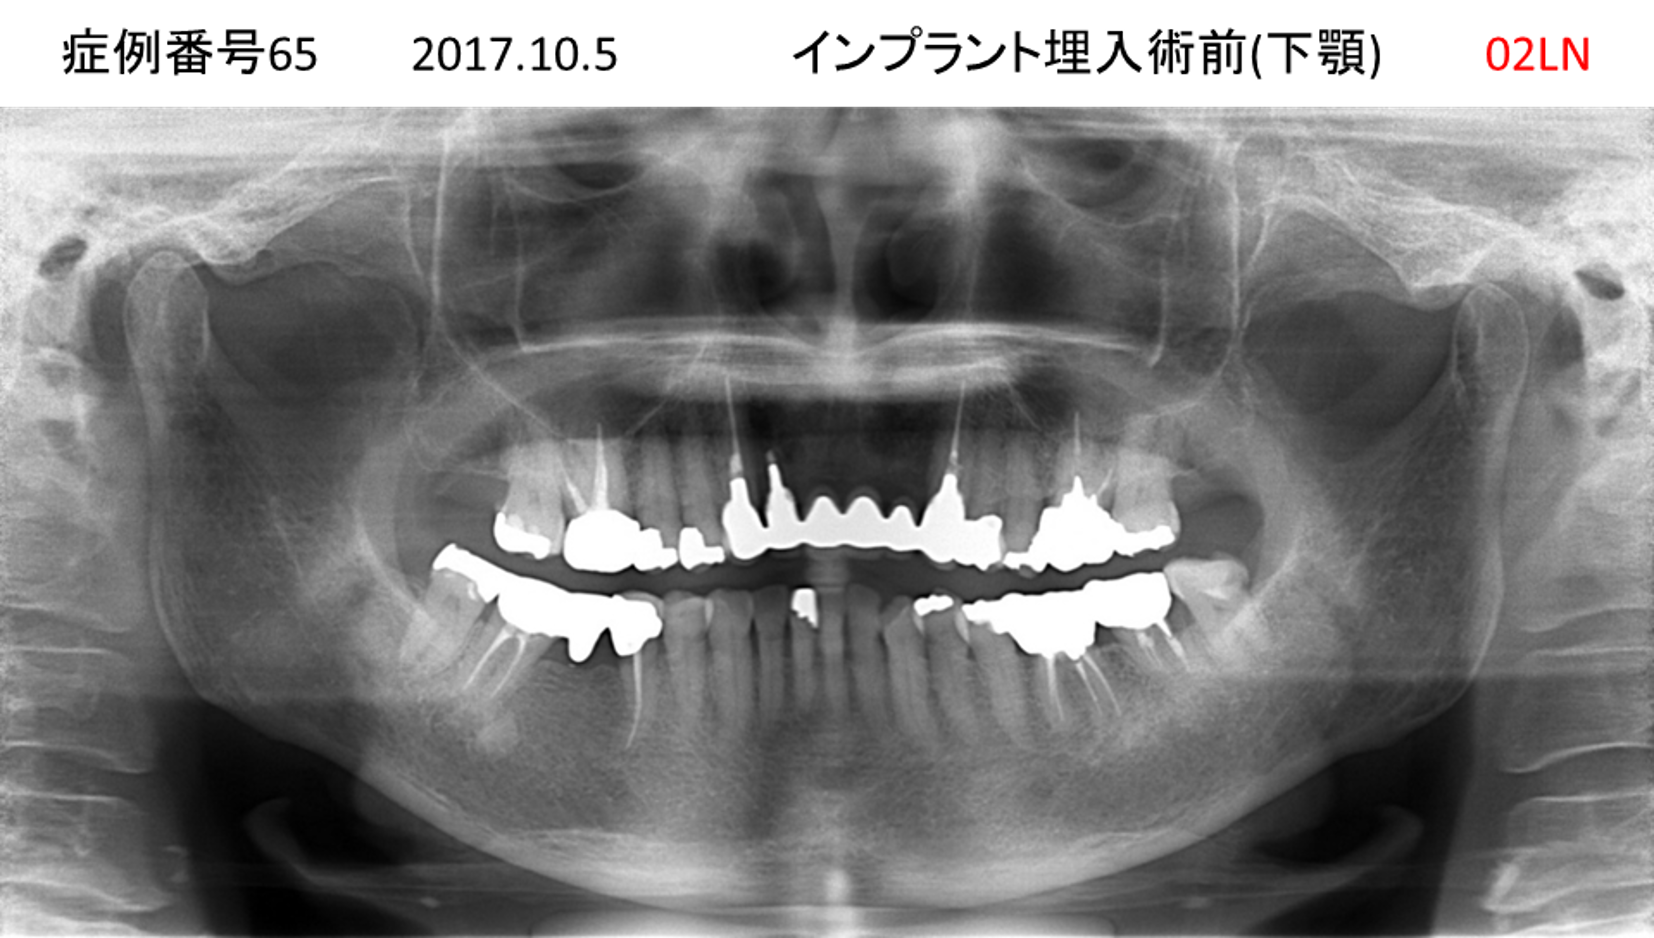

揺れている歯が多くて噛めない患者様のインプラント症例

| 治療名称 |

インプラント |

| 治療費用 |

440万円+税 |

| 治療期間 |

8か月 |

| 患者さんの症状(主訴) |

上の歯をはじめ、揺れている歯が多くて噛めない。食事ができない。 |

| 治療内容 |

サイナスリフト 抜歯即時インプラント |

| 治療結果 |

食事に困らない。見た目がとても良くなった。 |

| 治療の注意点(リスク/副作用) |

インプラントが壊れたら再治療が必要 |